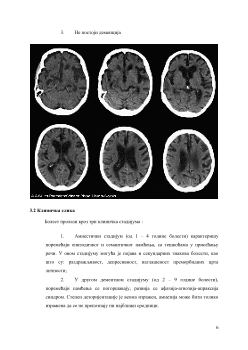

4.